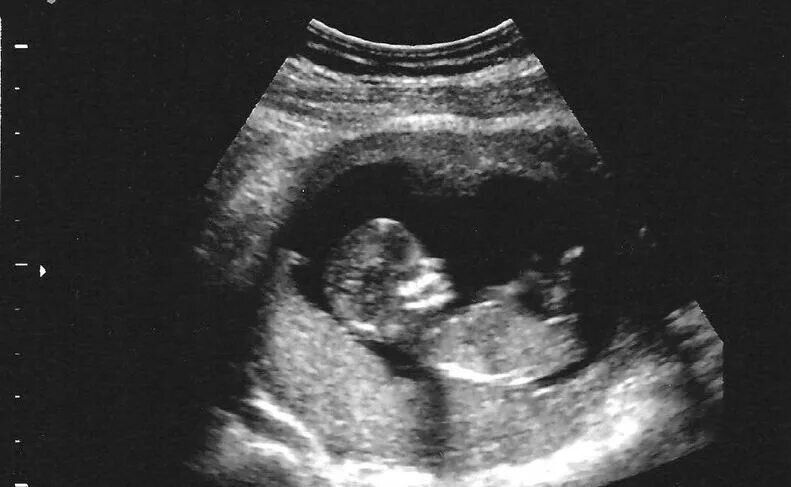

Первое УЗИ показало сразу, что у нас мальчик. Обычная ни чем не примечательная беременность.. Всё по плану: анализы, скрининги, плод в полном порядке, не тошнит, не мутит. Всё отлично.

Из открытых источников.